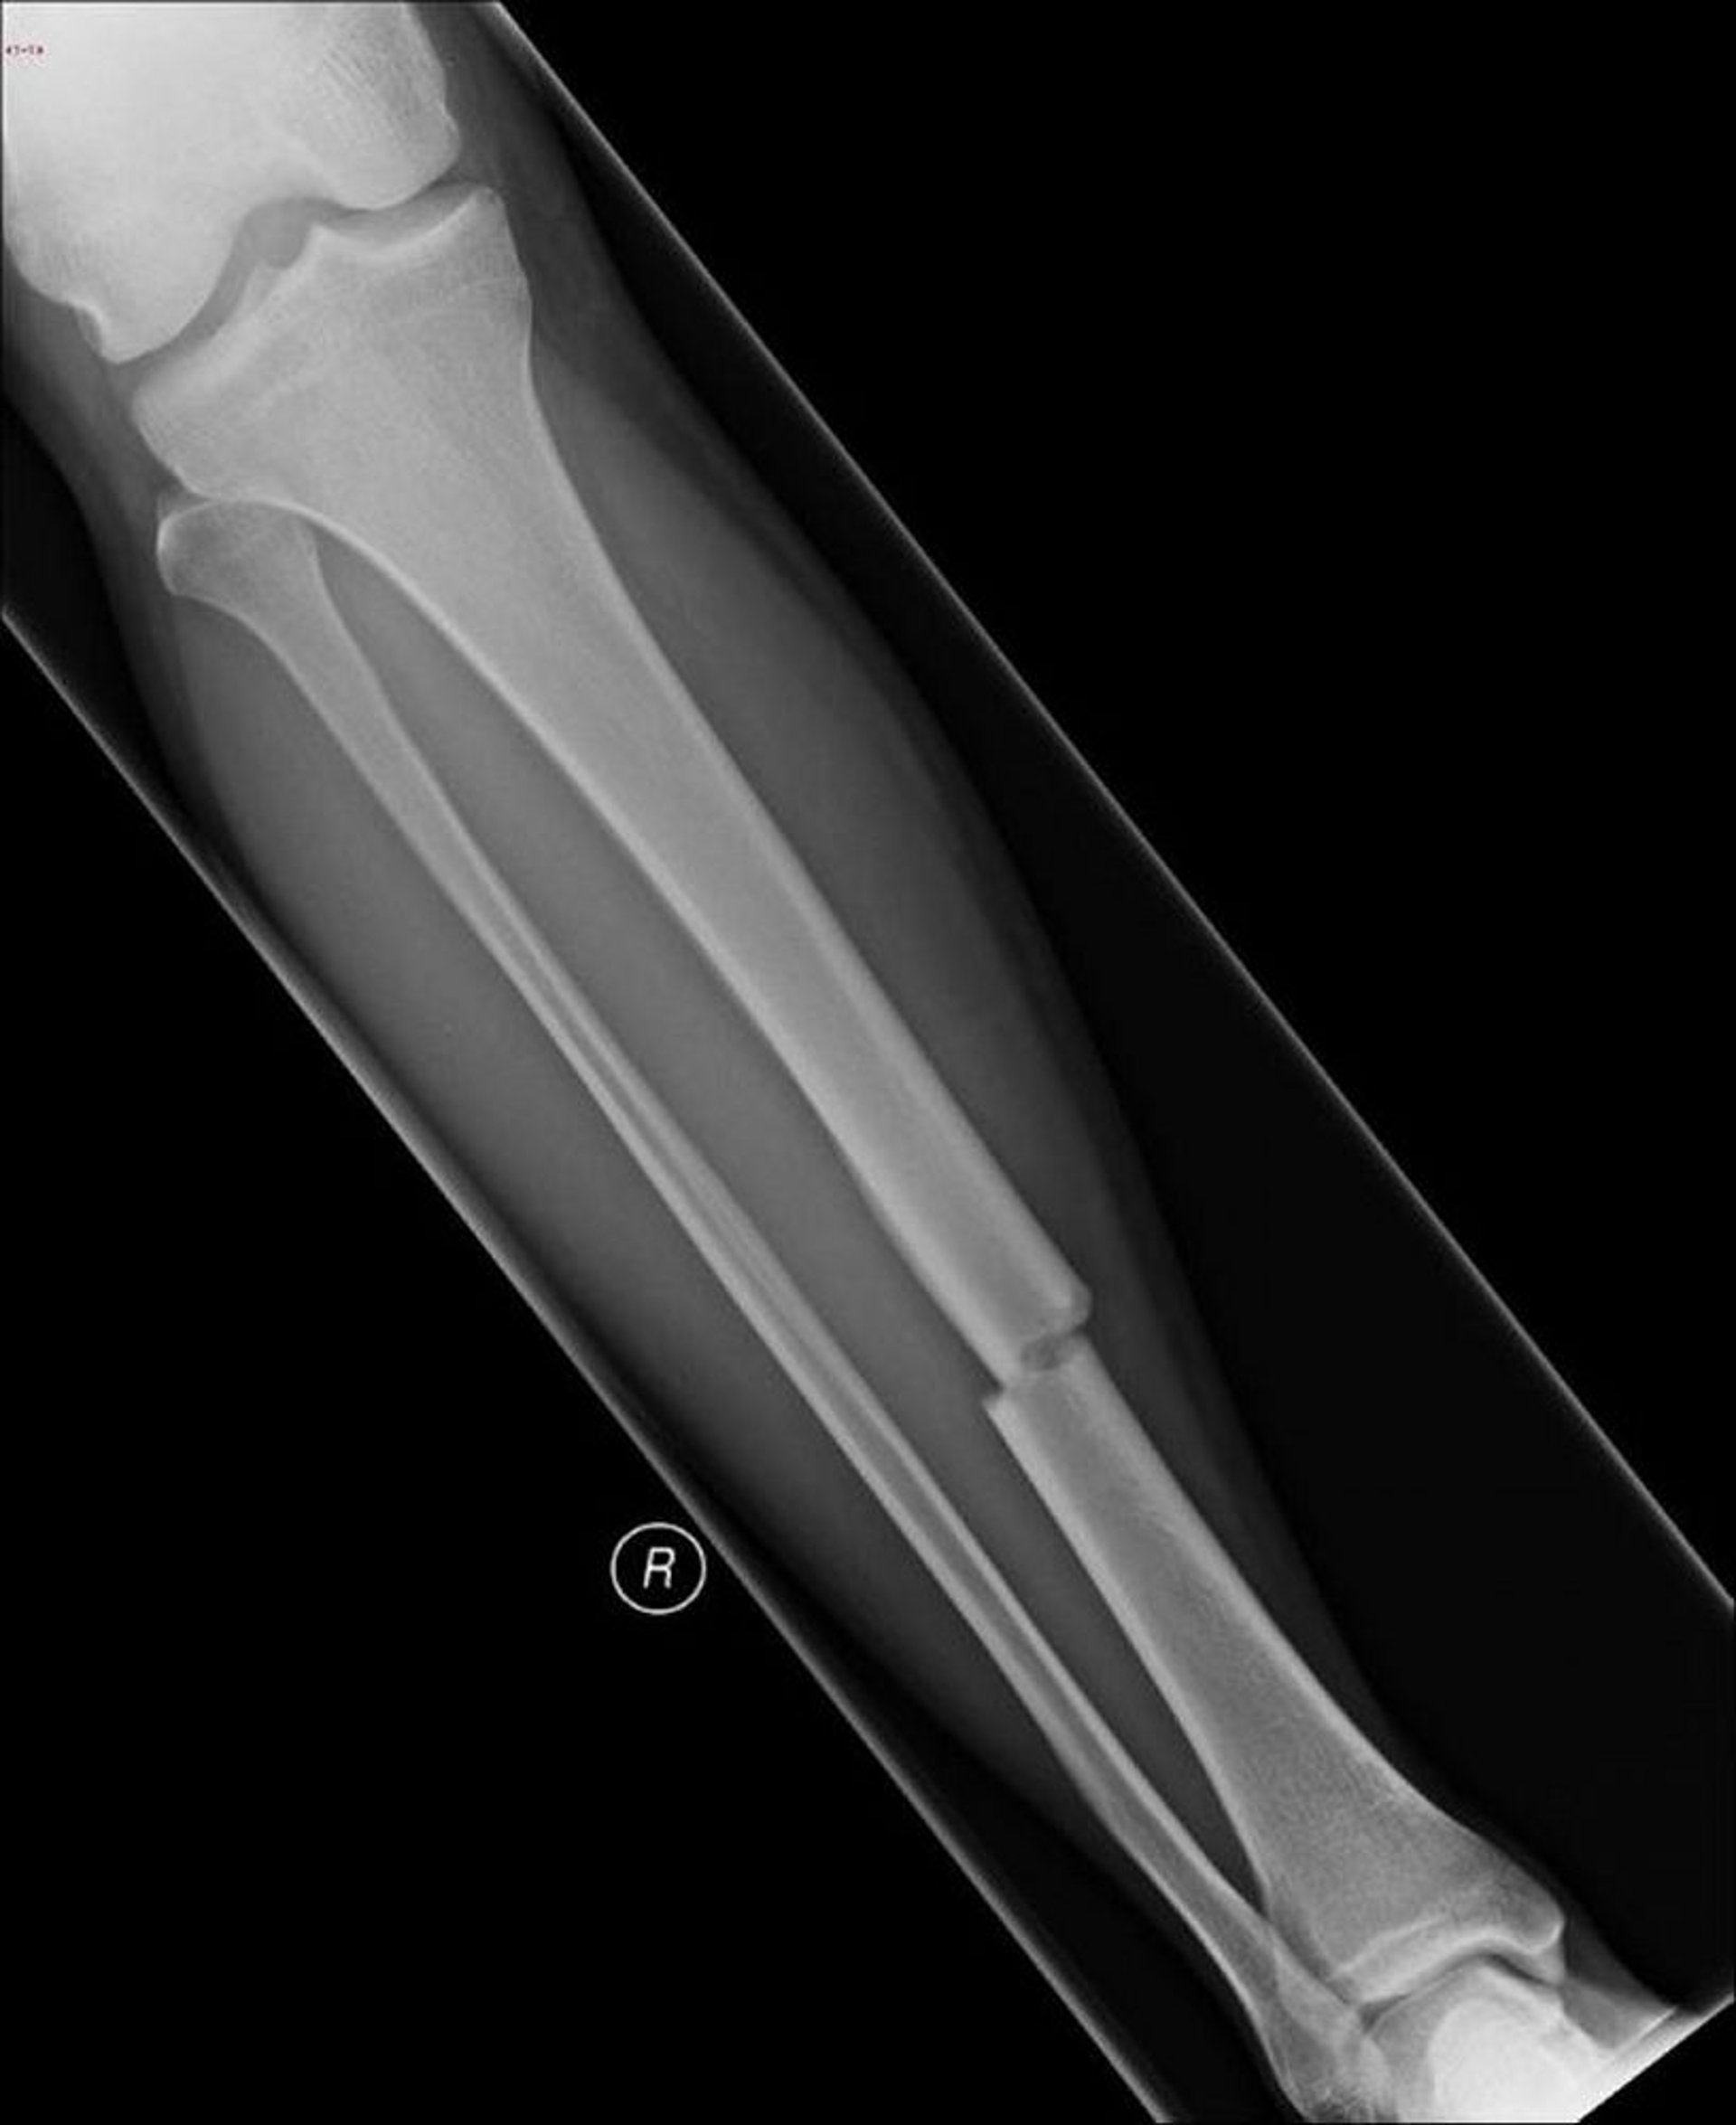

Querfraktur des Tibiaschafts

Diese transversale Fraktur betrifft den mittleren Schaft der Tibia.